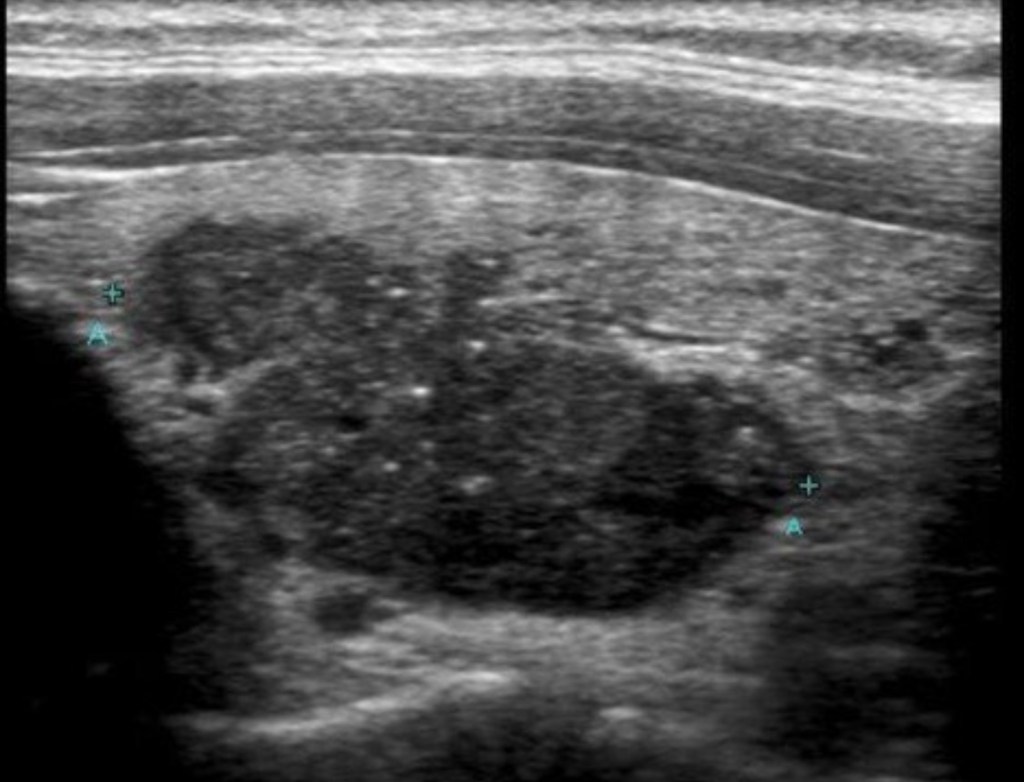

The most important first step is a high-resolution thyroid ultrasound, which allows us to:

Accurately measure and characterize nodules Assess features associated with cancer risk Use validated risk-stratification systems (ATA / TI-RADS) Decide whether a biopsy is actually necessary